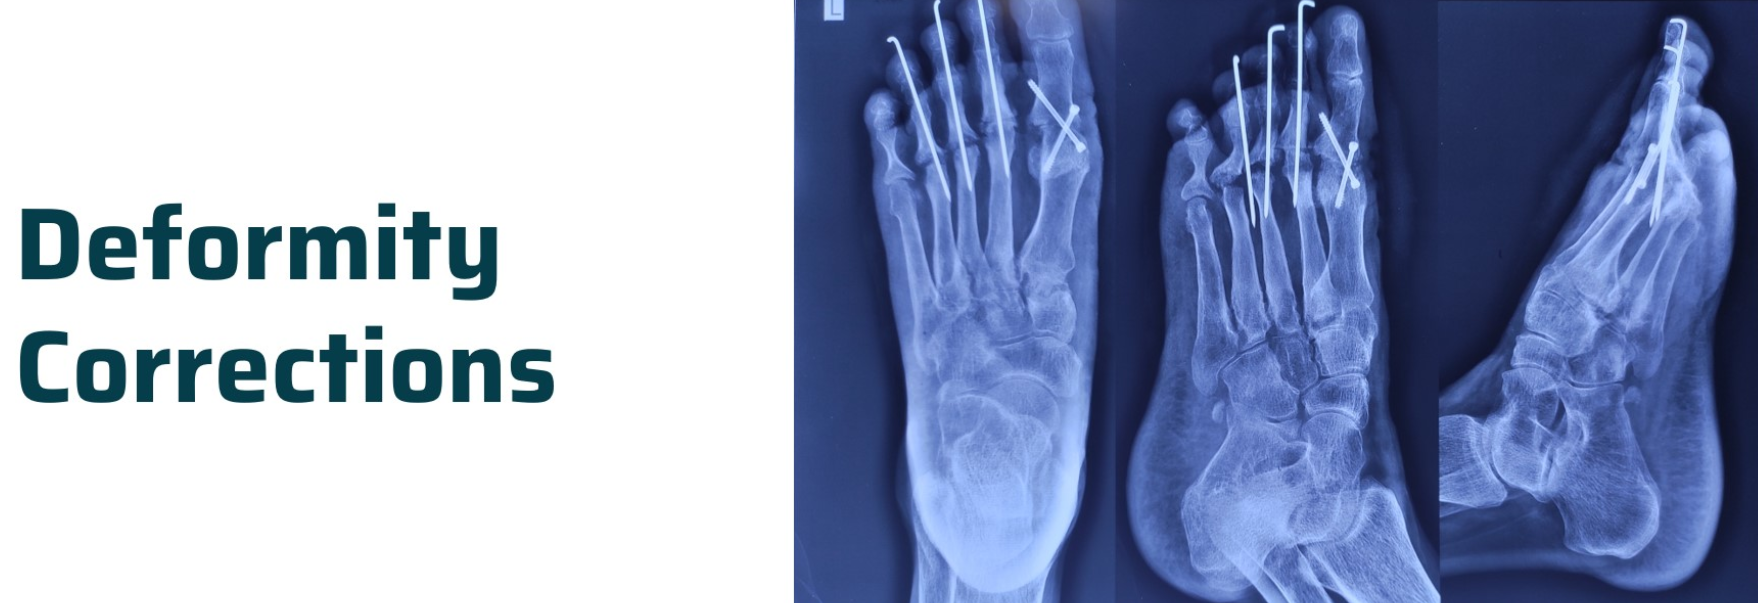

X-rays: Standard imaging for evaluating bone structure and deformity angles (e.g., Cobb angle for scoliosis).

Osteotomy (Bone Cutting and Realignment):

The surgeon cuts and repositions the bone to correct angular or rotational deformities. Plates, screws, or rods stabilize the corrected bone. -

Internal Fixation with Plates and Rods:

Internal implants provide rigid stabilization after osteotomy or fracture realignment. -